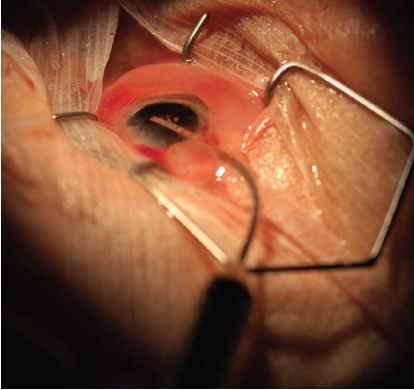

The ECP procedure is performed using a handheld laser endoscope connected to a laser endoscopy unit (Endo Optiks Laser Endoscopy; BVI) (Figure 1). The handheld unit contains three optical fibers, incorporating an image guide, light guide, and laser guide.

Figure 1. Laser endoscope with curved probe.

The probe is inserted through the incision (Figure 2), and the surgeon views the procedure on a monitor and begins to apply laser to the ciliary processes. The energy is slowly increased until shrinkage and whitening of the ciliary processes can be seen (Figure 3).11

Figure 2. Laser endoscope probe inserted into the anterior chamber through a corneal incision.